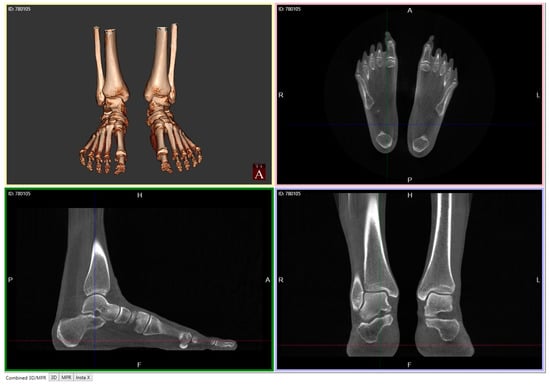

Recent Innovations Brought about by Weight-Bearing CT Imaging in the Foot and Ankle: A Systematic Review of the Literature

3. Results